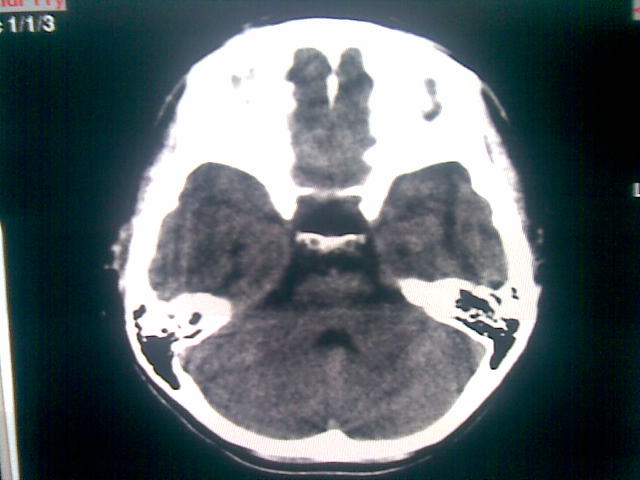

以下是引用随光逐影在2010-1-5 16:32:00的发言:[br]1)鞍上池囊性占位性病变,不排除蛛网膜囊肿可能;建议行mri检查。2)脑积水。

以下是引用yangyang2000在2010-1-5 20:41:00的发言:[br])鞍上池囊性占位性病变,不排除蛛网膜囊肿可能;建议行mri检查。2)脑积水

以下是引用yangyudong333在2010-1-5 21:28:00的发言:[br]1)鞍上池囊性占位性病变,不排除蛛网膜囊肿可能;建议行mri检查。2)脑积水。